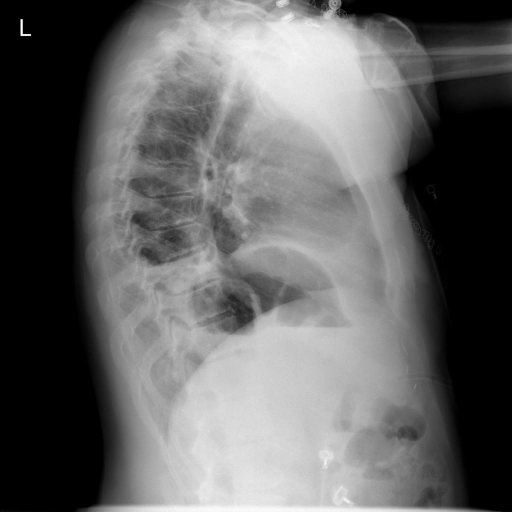

In conventional chest X-Ray exams, the erect patient is positioned between an X-Ray tube and a detector. The collected data by the detector is then used to create a comprehensive image. The main distinctions in positioning (such as anteroposterior (AP) and posteroanterior (PA), both of which we refer to a Frontal, or lateral (L)), are related to which view enables the most insight.

We compare our projected X-Rays with samples from the OpenI dataset for frontal and lateral views in Figure 5. The differences in the frontal view are due to the different positioning of the shoulder girdle. In the X-Rays, the arms are usually placed alongside the body, while in the projected images, the arms are raised due to the nature of the CT scan. In the lateral view, the X-Rays show a more comprehensive range of orientation and pose. However, the projected images, typically taken while the patient is lying down, result in similar poses between the different images. This leads to visual differences between images of female patients in both frontal and lateral views, such as the third column and second row of real X-Ray images and the first column and second row of projected images.